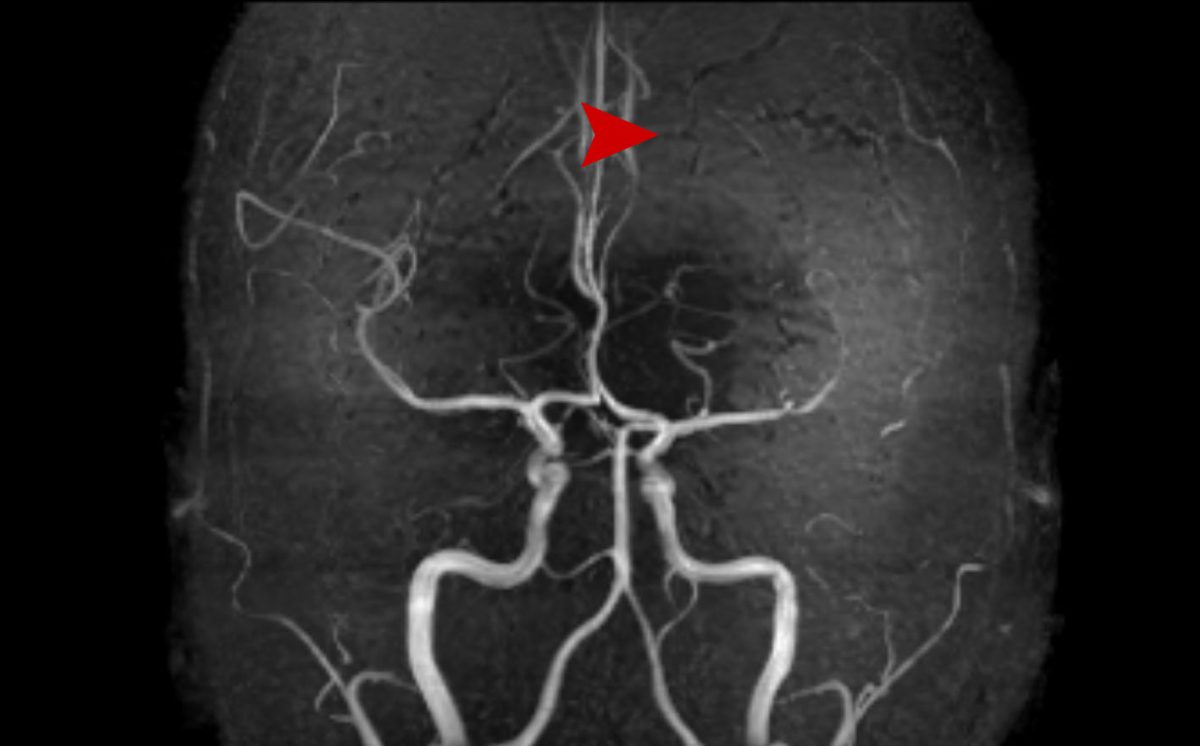

Θήλυ 30 ετών με αιμορραγείσα αρτηριοφλεβώδη δυσπλασία εγκεφάλου (AVM) αριστερά μετωπιαία. Σύγκριση MRA 1/2018 με 12/2019. Πλήρης εξάλειψη της δυσπλασίας.

Μετά την ακτινοχειρουργική θεραπεία με CyberKnife